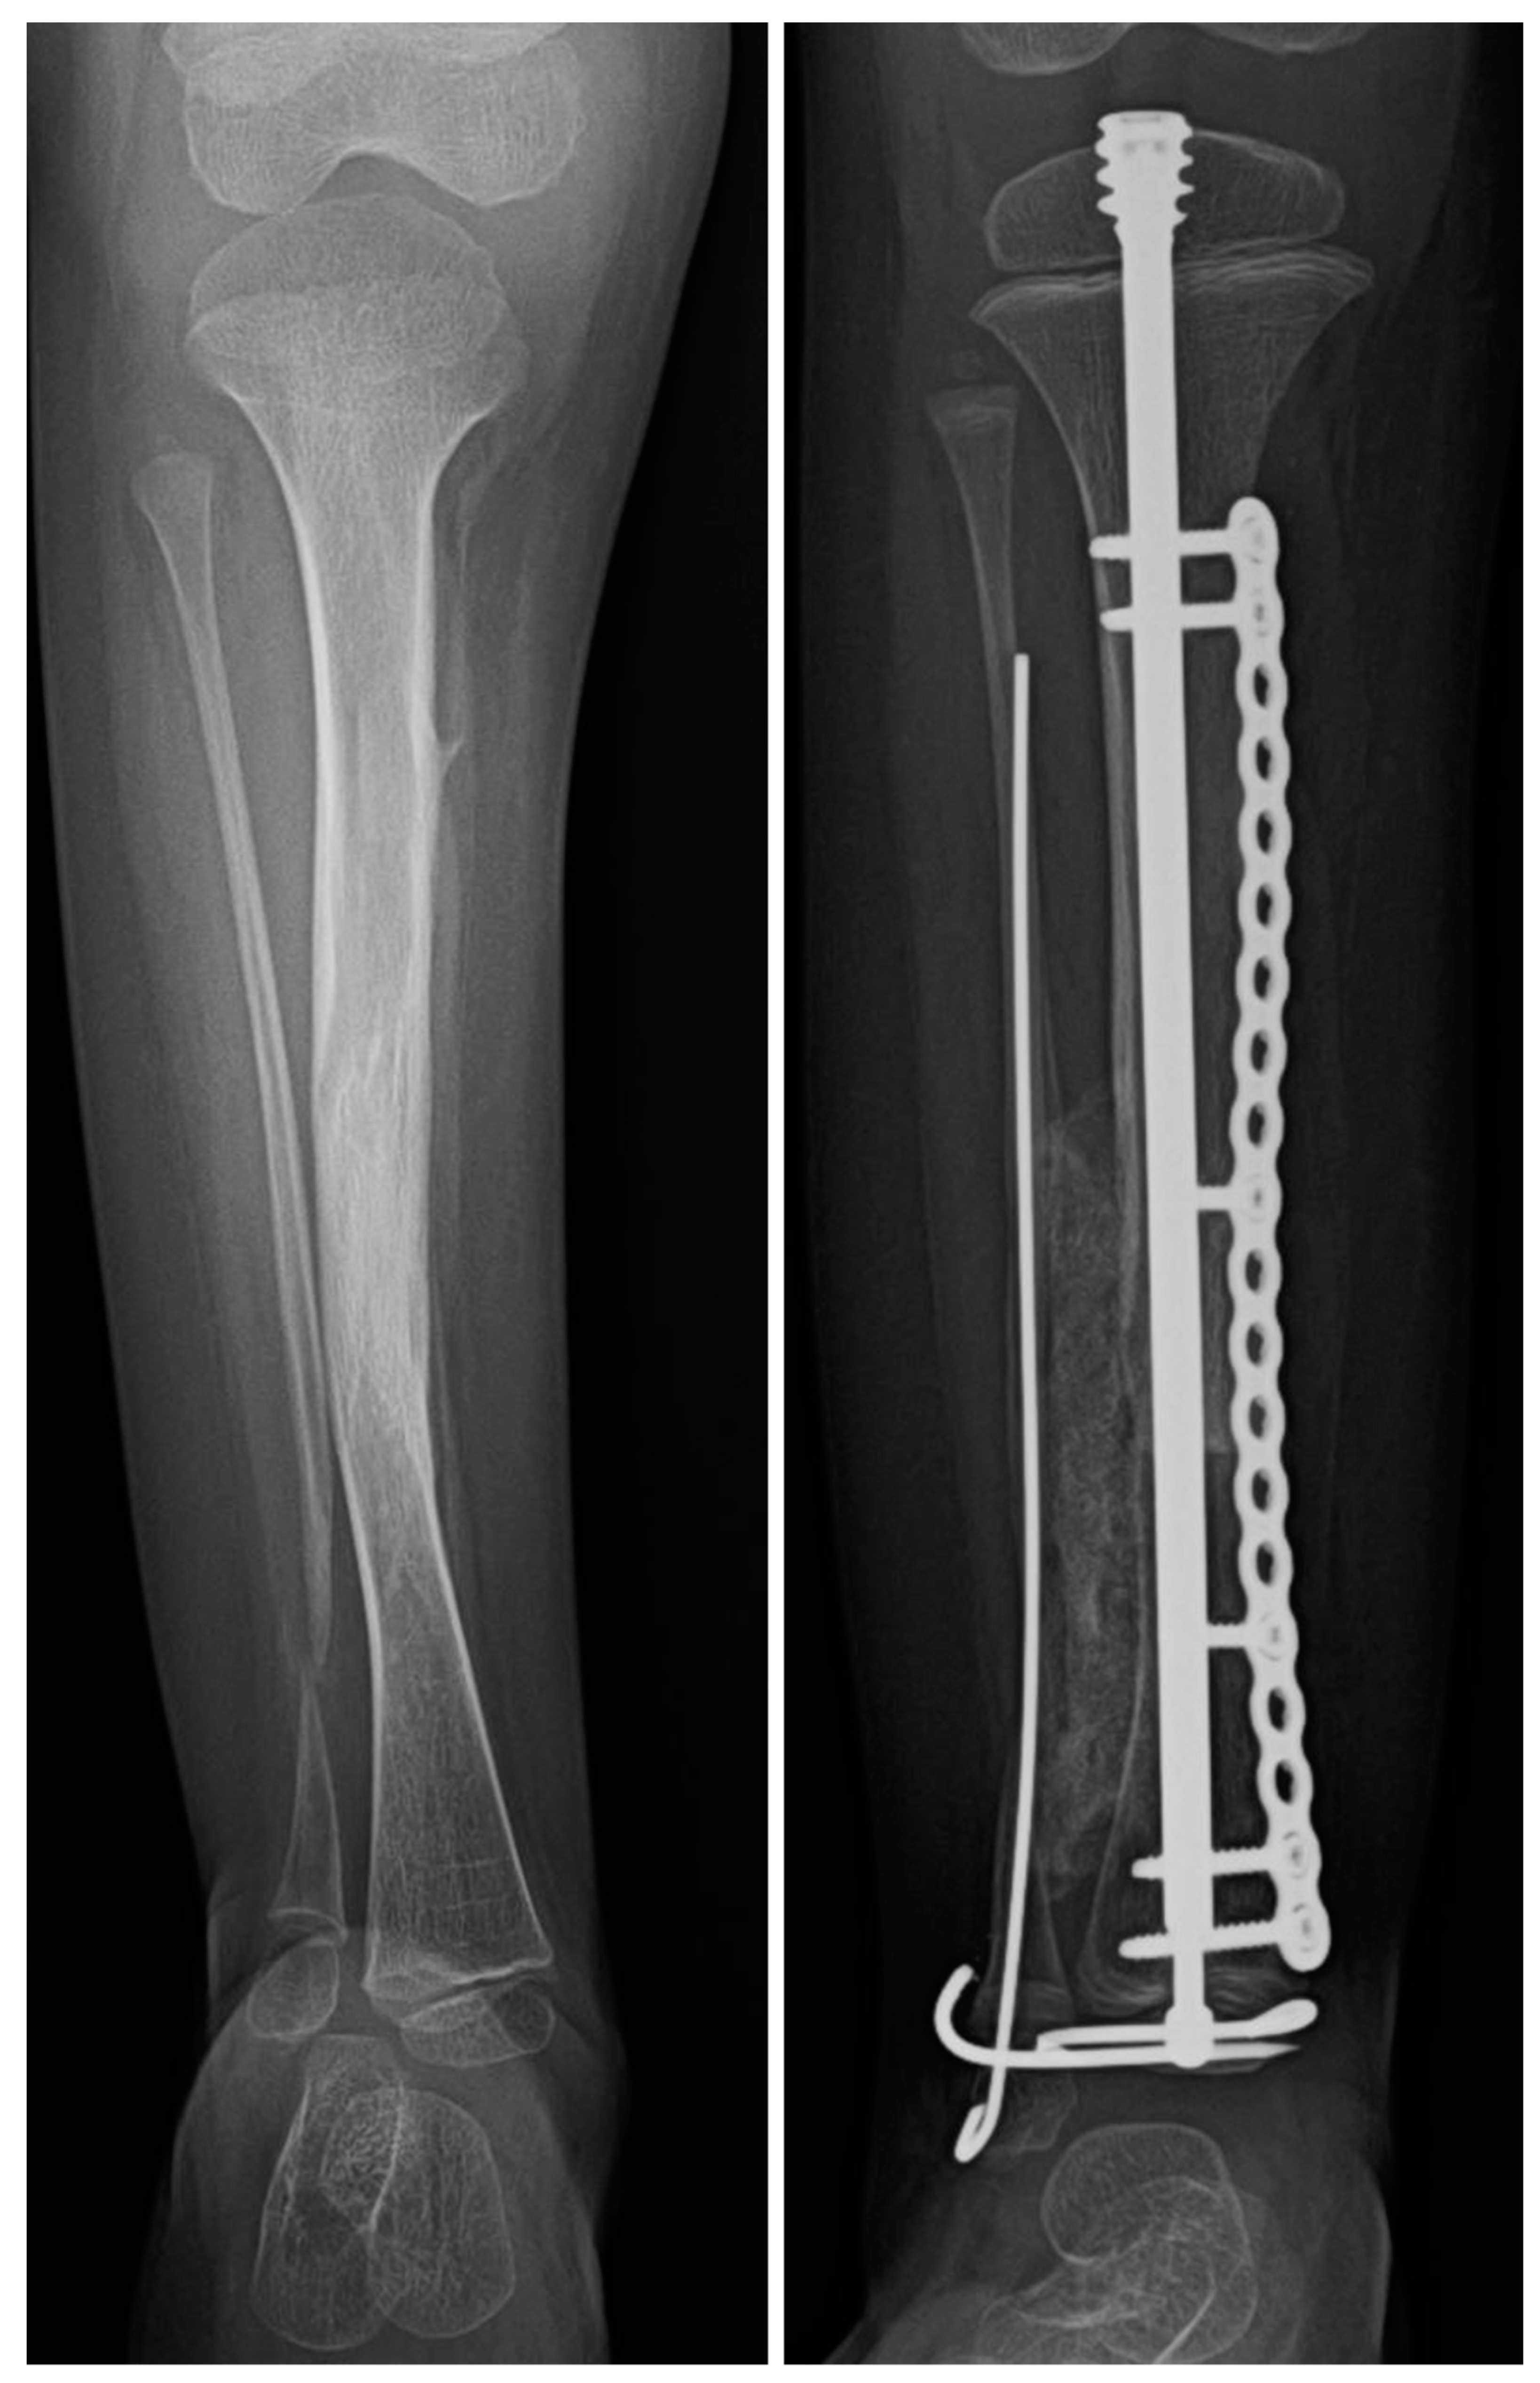

In 2011, Choi et al. [10] and in 2012, Paley [11] independently published their respective methods of treating patients with CPT by creating an intentional cross-union between the tibia and fibula. Choi et al. did this by converging the fibula towards the tibia, bone grafting between them and fixing the tibia by IM rodding across the ankle joint and circular external fixation (4-in-1 technique). Paley achieved this by rodding both bones straight without crossing the ankle and bone grafting between the tibia and fibula to create a wide bridge of bone, applying a circular external fixator, using bone morphogenic protein 2 (BMP2) intraoperatively and using Zoledronic Acid preoperatively and 3 months postoperatively (Paley cross-union protocol) (Figure 1A). Both achieved union in all cases without refracture. This 100% success rate of union without refracture was double that of all previous methods. Furthermore, the age at the time of treatment was not a limitation to success. In 2019, Paley published a modification of his original method substituting a malleable plate on the tibia for the circular external fixator [8] (Figure 1B). The Paley cross-union protocol was published with step-by-step illustrations in the supplement to this article [12]. The purpose of this study is to examine the early results of the Paley cross-union protocol using only internal fixation (no external fixation).

Figure 1. (A) AP and lateral radiographs that were taken postoperatively of a patient who underwent a Paley cross-union procedure performed with a circular external fixator. (B) AP and lateral radiographs that were taken postoperatively of a patient who underwent a Paley cross-union procedure performed with all internal fixation.